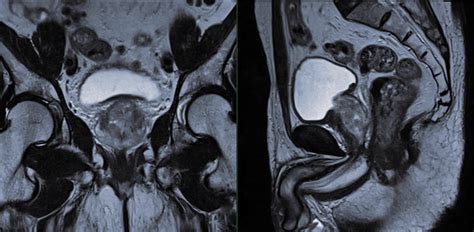

• Size and Shape of the Prostate: The MRI can show the overall size and shape of the prostate, which can indicate conditions like BPH.

• Tumors or Lesions: The presence of tumors or lesions within the prostate can be detected and characterized based on their size, shape, and location.

• Extracapsular Extension: MRI can determine if the cancer has spread beyond the prostate capsule, which is crucial for staging and treatment planning.

• Lymph Node Involvement: The MRI can also assess nearby lymph nodes for signs of cancer spread.